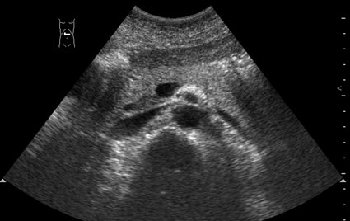

Гипостеатоз крючковидного отростка панкреас

Пациент 35 лет, без жалоб, профилактический осмотр.

По задней поверхности головки панкреас имеется участок сниженной эхогенности.

Цитата: "The hypoechoic area is located posteriorly in the head and typically shows a straight and clear demarcation. This demarcation line corresponds to the level of fusion between both embryonal ventral and dorsal portions of the pancreas. In accordance with the structural differences that have been described between the embryologically derived ventral and dorsal pancreatic portions , has shown that the ventral portion of the pancreas may appear hypoechogenic because more rich of fatty tissue compared to the dorsal portion."

считаю вариант нормы,так выглядит процессус унцинатус в норме